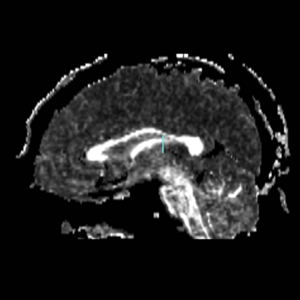

Boundaries for the ROI's, mainly using FA maps & color by orientation, followed by the color coding of the labelmaps.

IC - Internal CapsuleROI 1) find anterior commisure on axial view and draw ROI on coronal slice on each side on midsag line Top boundary for ROI 1: Caudate/putamen line Bottom boundary for ROI 1: draw entire plane of AC; IC is only superior to AC line. ROI 2) go to the anterior most point of the corpus collosum according to saggital view. Draw ROI so it covers entire (left or right) hemisphere of brain on the perpendicular Coronal Slice.